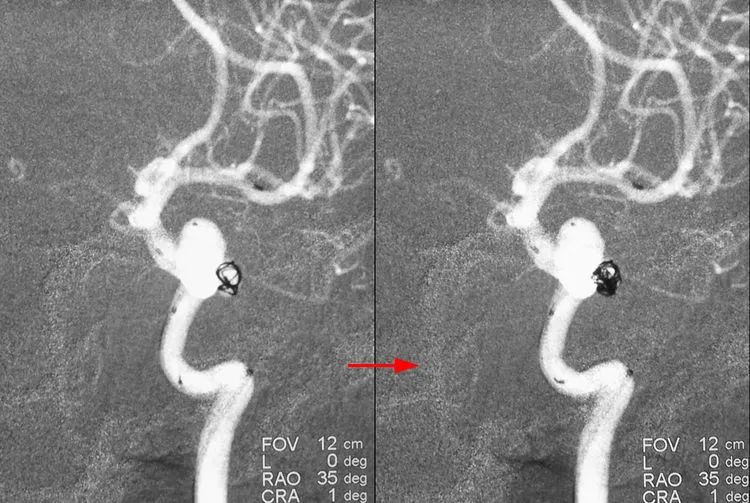

LVIS支架(3.5-15)辅助下双微管栓塞动脉瘤,先经甲管向大分叶内依次填入5枚弹簧圈(QC-6-15-3D,4-12-HELIX,3-8-HELIX,3-8-HELIX,2-8-HELIX),少量弹簧圈挤入小分叶;再经乙管向小分叶内依次送入3枚弹簧圈(APB-3-8-3D-ES,2-6-HX-ES,1.5-4-HX-ES);最后继续经乙管送入3枚弹簧圈(APB-1.5-3-HX-ES,1-3-HX-ES,1-3-HX-ES)封闭瘤颈:

术后左颈内动脉工作位造影显示动脉瘤完全栓塞,后交通动脉壶腹保留: